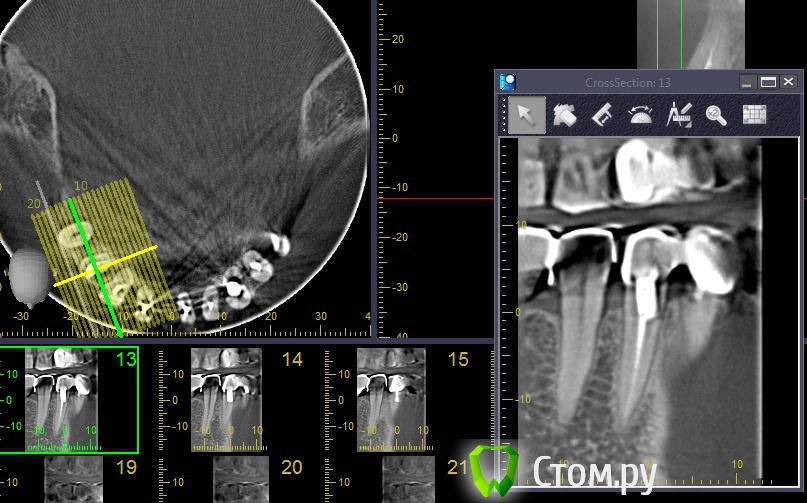

stradalitca Опубликовано 20 мая, 2014 Автор Поделиться Опубликовано 20 мая, 2014 (изменено) Добрый вечер! Я тут ещё глянула как установлен штифт на четвёрке снизу справа. Вот фото в проекциях. Неужели зуб тоже пробит штифтом? или пойдёт ? и я зря переживаю. Изменено 20 мая, 2014 пользователем stradalitca Ссылка на комментарий

Korel Опубликовано 23 мая, 2014 Поделиться Опубликовано 23 мая, 2014 Неужели зуб тоже пробит штифтом? Похоже на то. А Вы не рассматривали для Вашей мамы вариант (на н\чел.) бюгельный протез с замковыми креплениями. 1 Ссылка на комментарий

stradalitca Опубликовано 23 мая, 2014 Автор Поделиться Опубликовано 23 мая, 2014 почитала про мплантанты. Получается, что нам это не особо подходит. Начиная с того, что надо вылечить всю остальную челюсть - то есть убрать очаги воспаления. А воспаление видно невоооружённым глазом. Сегодня у неё стала кровить нижняя четвёрка справа. то ли от полосканий солью, то ли дают знать о себе очередной неудавшийся штифт.А бюгельный протез Вы предлагаете на место моста из 9 коронок и плюс 5,6,7 слева? я правильно поняла? Ссылка на комментарий